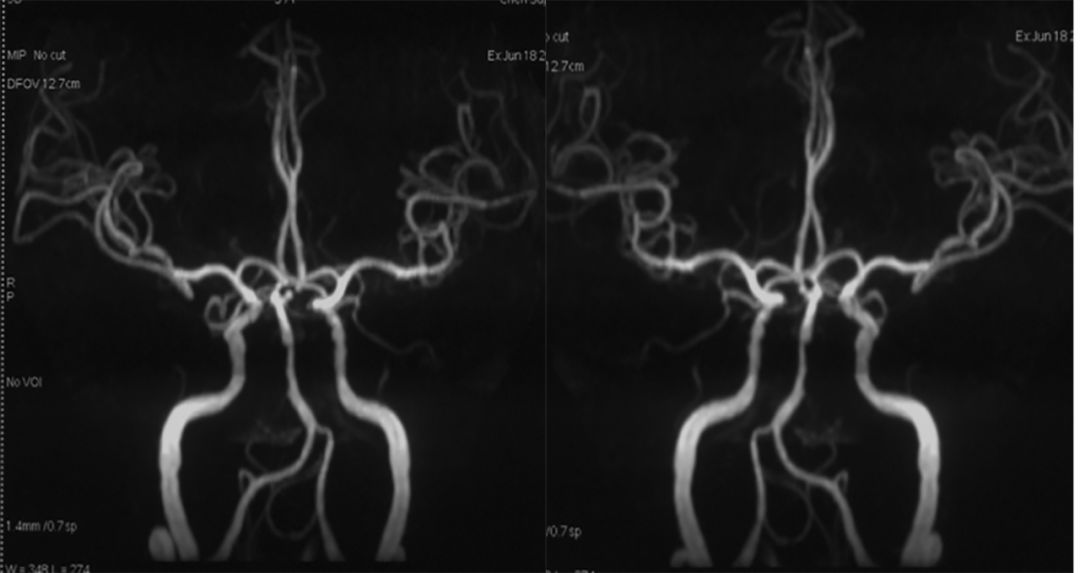

头MRA (2019-6-18 ,*** 人民医院):基底动脉末端动脉瘤,基底动脉中段狭窄(图2)。

图2

头颅CTA(2019- 6-18 ,*** 人民医院):基底动脉末端左侧小脑上动脉瘤,基底动脉中段狭窄(图3)。

图3